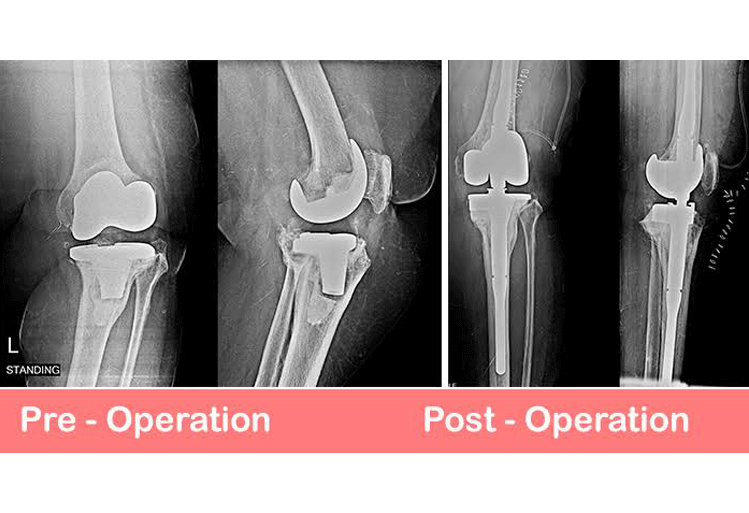

Total Knee Joint Replacement (TKR) revision surgery is an orthopaedic surgical procedure in which the prosthetic pieces(s) of the previous TKR surgery are removed. New prosthetic pieces are then replaced within the knee joint. The components consist of the femoral condyle component, the tibial plateau component, the polyethylene spacer and the patella component. All or some of these may be replaced depending on the reason for replacement.

Revisional TKR surgery is a more complicated operation requiring longer time in theater and rehabilitation is slower and takes a more cautious approach.